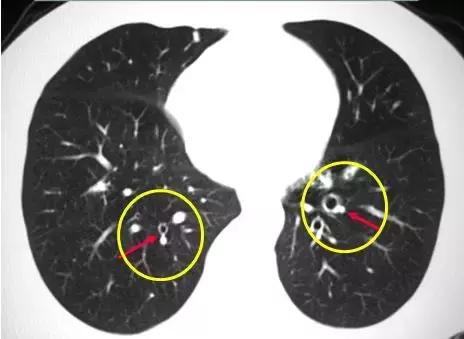

CT征象二:轨道征与印戒征

1、“轨道征”:扩张支气管走行与CT扫描平面平行时

2、“印戒征”:扩张支气管与CT扫描层面垂直时

(正常同级别的肺动脉直径稍大于伴行的支气管内径)

CT表现:在肺野内显示为平行的线样高密度影或环形低密度影伴周围点状高密度影(直径小于前者)

意义:表明有支气管扩张、慢性支气管炎伴发的细支气管扩张等。

柱状支气管扩张与扫描层面垂直——“印戒征”